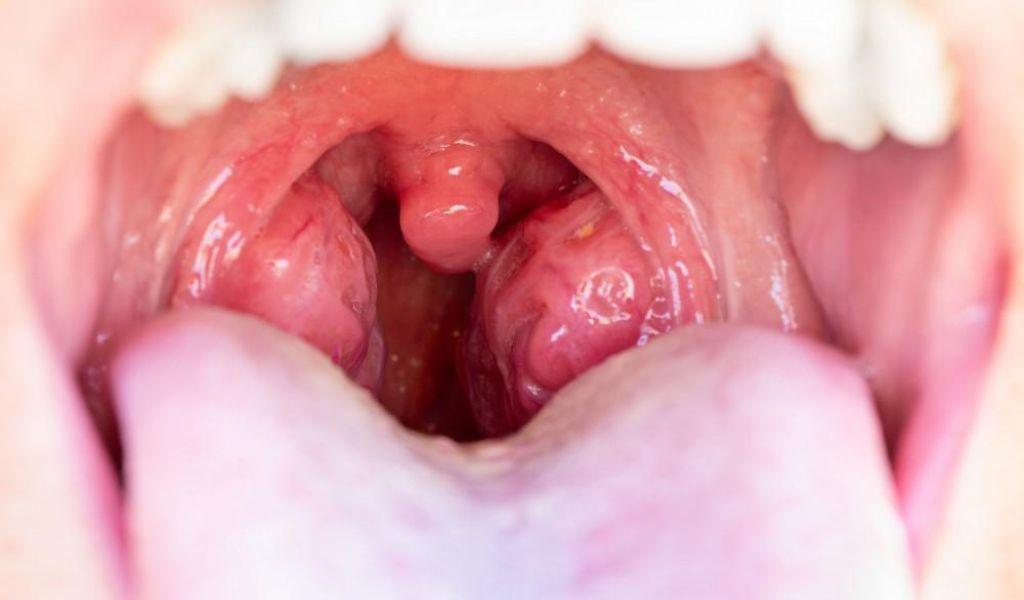

Khi bị viêm, amidan có thể sưng đỏ, đau rát, khiến trẻ khó nuốt và dễ mệt mỏi. Bệnh thường gặp ở trẻ trong độ tuổi đi học do thường xuyên tiếp xúc với mầm bệnh, trong khi trẻ dưới 3 tuổi ít gặp hơn.

- Amidan sưng to hơn bình thường, tấy đỏ hoặc xuất hiện các đốm trắng, mủ nhỏ trên bề mặt. Đây là dấu hiệu điển hình cho thấy amidan đang bị nhiễm trùng.